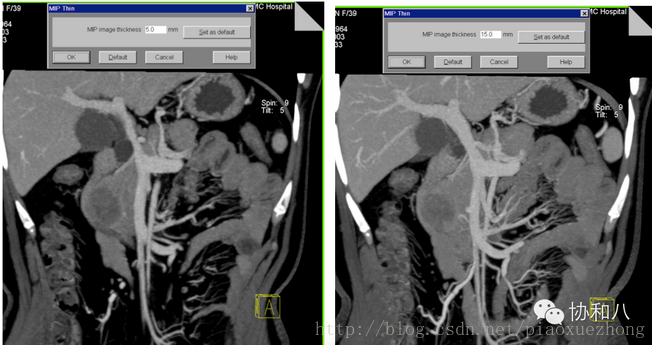

由于这种方法显示的是一定层厚图像中CT值最高的体素,所以变化层厚会对图像产生影响:

层厚5mm 层厚15mm

肿么样,是不是觉得层厚5mm的MIP图像上门脉有狭窄,而层厚15mm的MIP图像上门脉是正常的?

由于MIP常用来显示血管的走行(问我为啥常用来显示血管?因为增强CT上血管比周围组织器官亮啊~),所以层厚的选择很重要,既不能太薄(血管的部分管腔可能在层厚以外),又不能太厚(周围组织器官有干扰),这是很考验放射科大夫的技术和临床经验的。